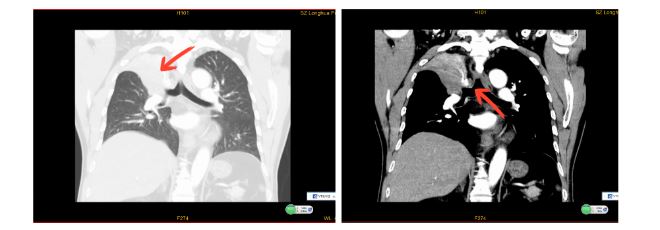

香港01引述《第一现场》报道,62岁的朱先生咳嗽伴气促已有4年,近半年病情加重。近日,他在龙华区人民医院呼吸与危重症医学科经支气管镜检查并活检,确诊为小细胞肺癌,医院于是决定采用新技术——经支气管冷冻消融术为他治疗。

手术当天下午麻醉科主治医师谢凌峰麻醉成功后,呼吸内科主任沈观乐在余瑞林副主任医师配合下,顺利插入硬质支气管镜,再通过软镜下置入一次性软性冷冻消融针,在导管推动下,经支气管精准到达癌变病灶,对肺结节实现冷冻消融,将癌细胞“冻死”。术后翌日,朱先生的咳嗽症状就明显缓和了。

而经支气管冷冻消融术,堪称是肺部肿瘤的“冰雕”技术。技术的核心在于使用一种特殊的冷冻消融设备,通过支气管途径将冷冻探针精确地送达肺部肿瘤的位置,利用超低温(通常达到零下150摄氏度)迅速冷冻并破坏肿瘤组织,从而达到治疗目的。